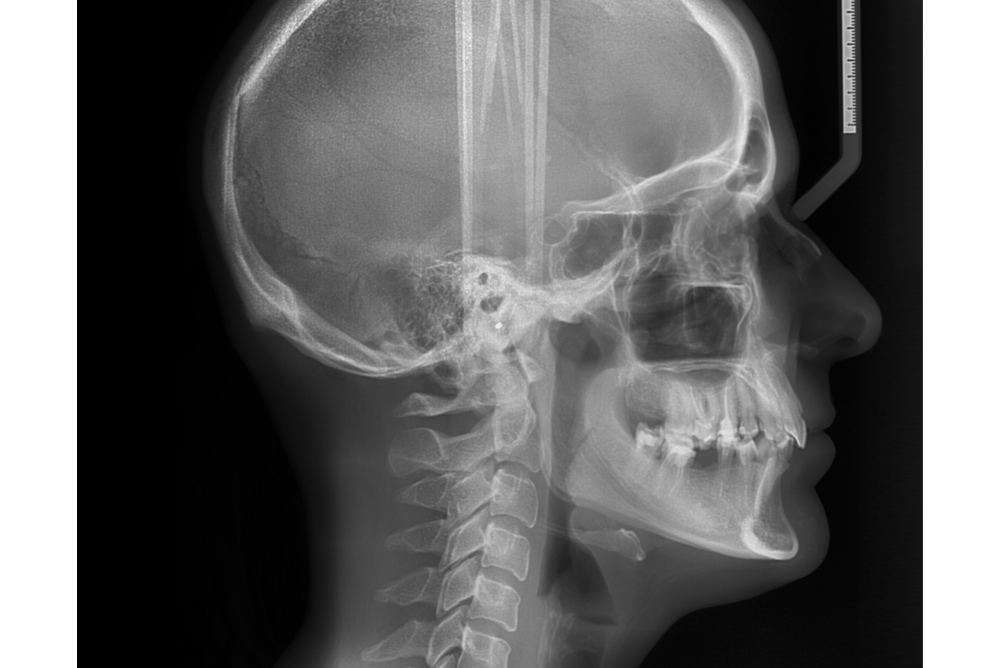

セファロ(頭部X線規格写真)

頭部や顔の骨格・歯並びのバランスを数値で分析できる矯正専用のレントゲンです。成長予測や治療計画の立案に欠かせない検査です。